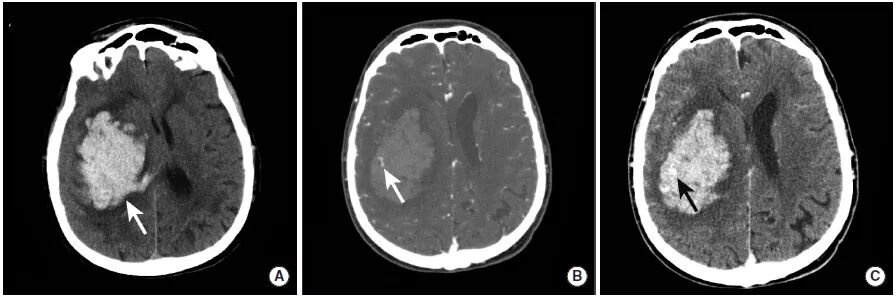

图7

本例高血压性

图A:

图B:CTA扫描动脉期显示点状高密度影(长尾箭头),即“点状征”。根据“点状征”的定义,点状强化为血肿边缘与血管不相连的高密度灶。

图C:CTA扫描延迟期显示活动性出血灶中与图B相同位置的高密度影(长尾箭头)。